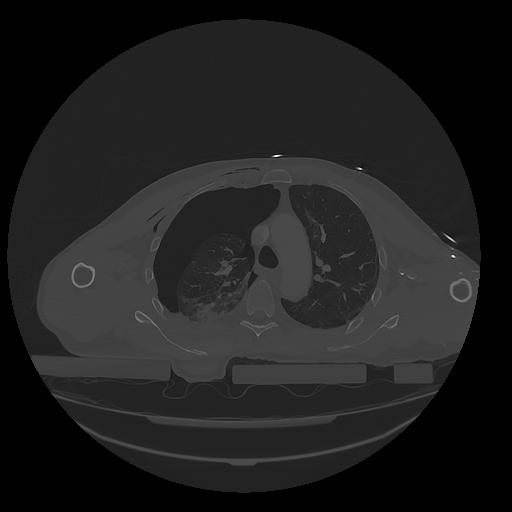

31 PULMON,CE,Vol,1.0,PULMON,,